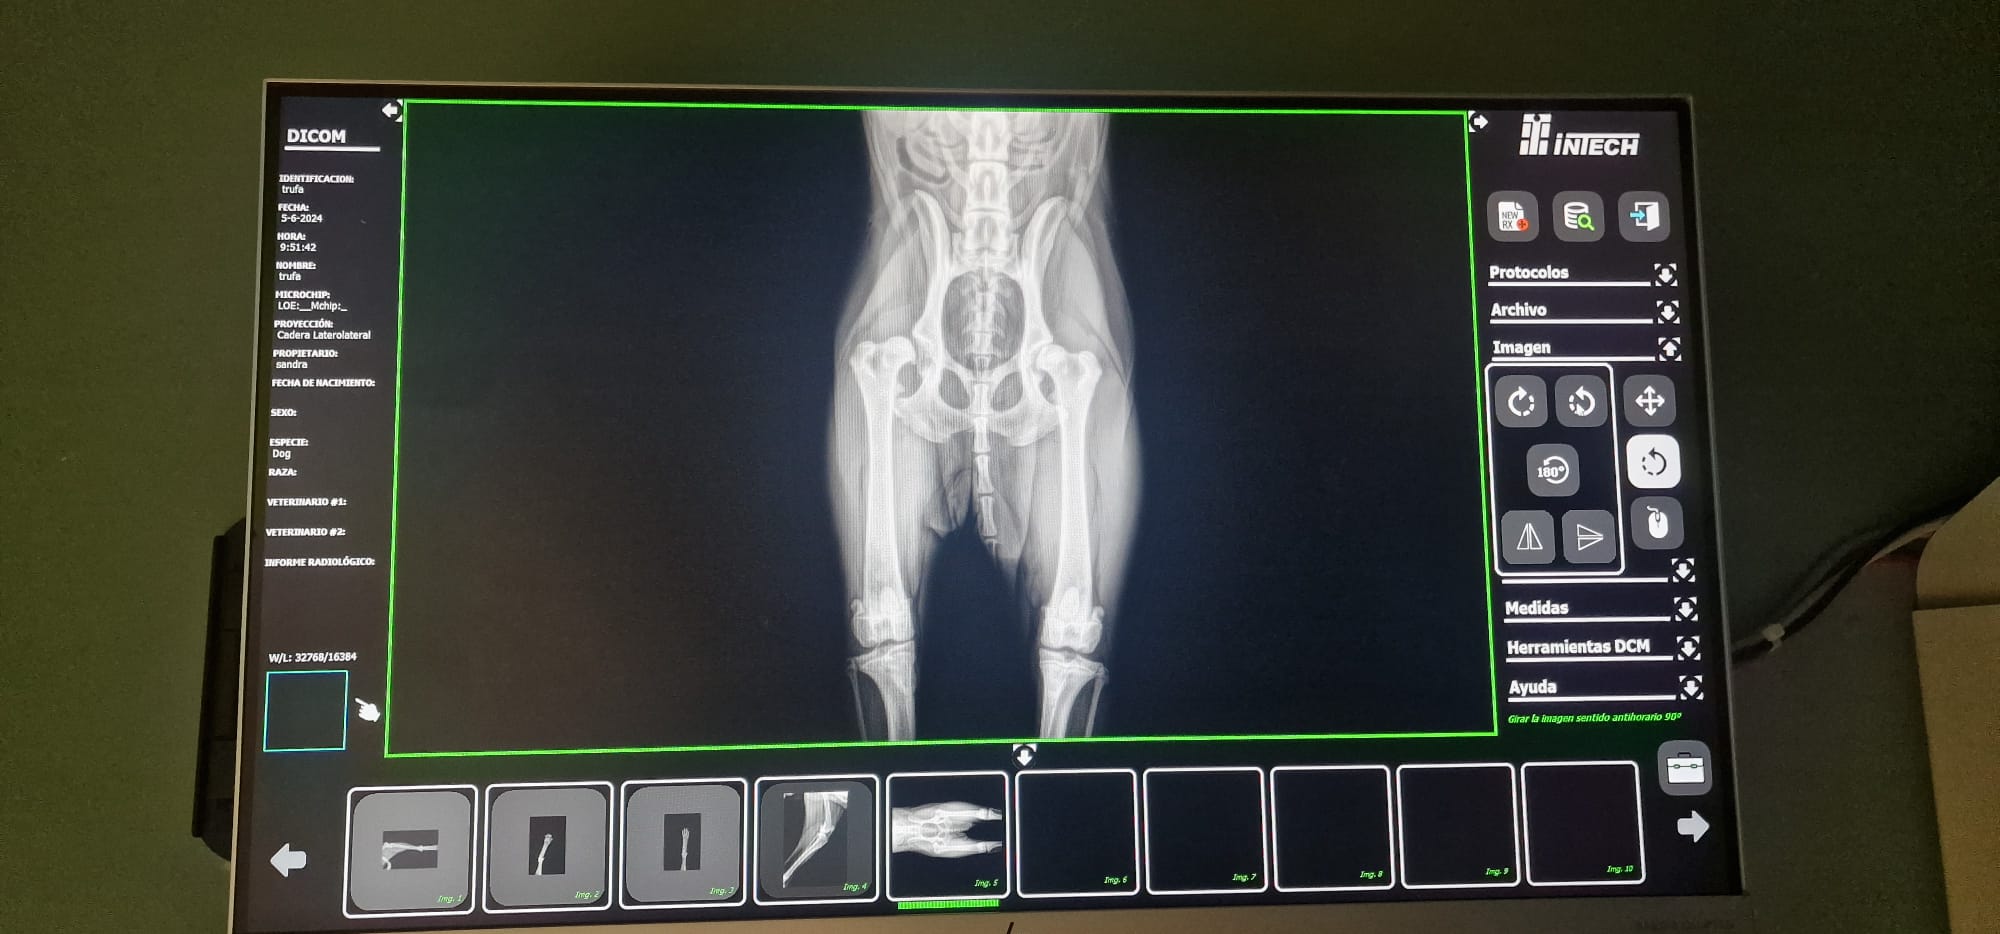

Radiografías = Salud en Imágenes 🐾🩺En Smile Vet, ofrecemos servicios de radiografías para cuidar la salud de tu mascota con precisión y cariño.

• Diagnóstico Rápido: Las radiografías nos permiten detectar problemas (óseos, dentales, respiratorios, cardiacos, etc.) y cuerpos extraños sin procedimientos invasivos. 🐶🐱

• Tecnología Avanzada: Utilizamos equipos modernos para obtener imágenes claras y detalladas, asegurando un diagnóstico eficaz.

• Cuidado Integral: Nuestro equipo interpreta los resultados para ofrecerte el mejor plan de tratamiento, siempre con el bienestar de tu mascota como prioridad. 🐾